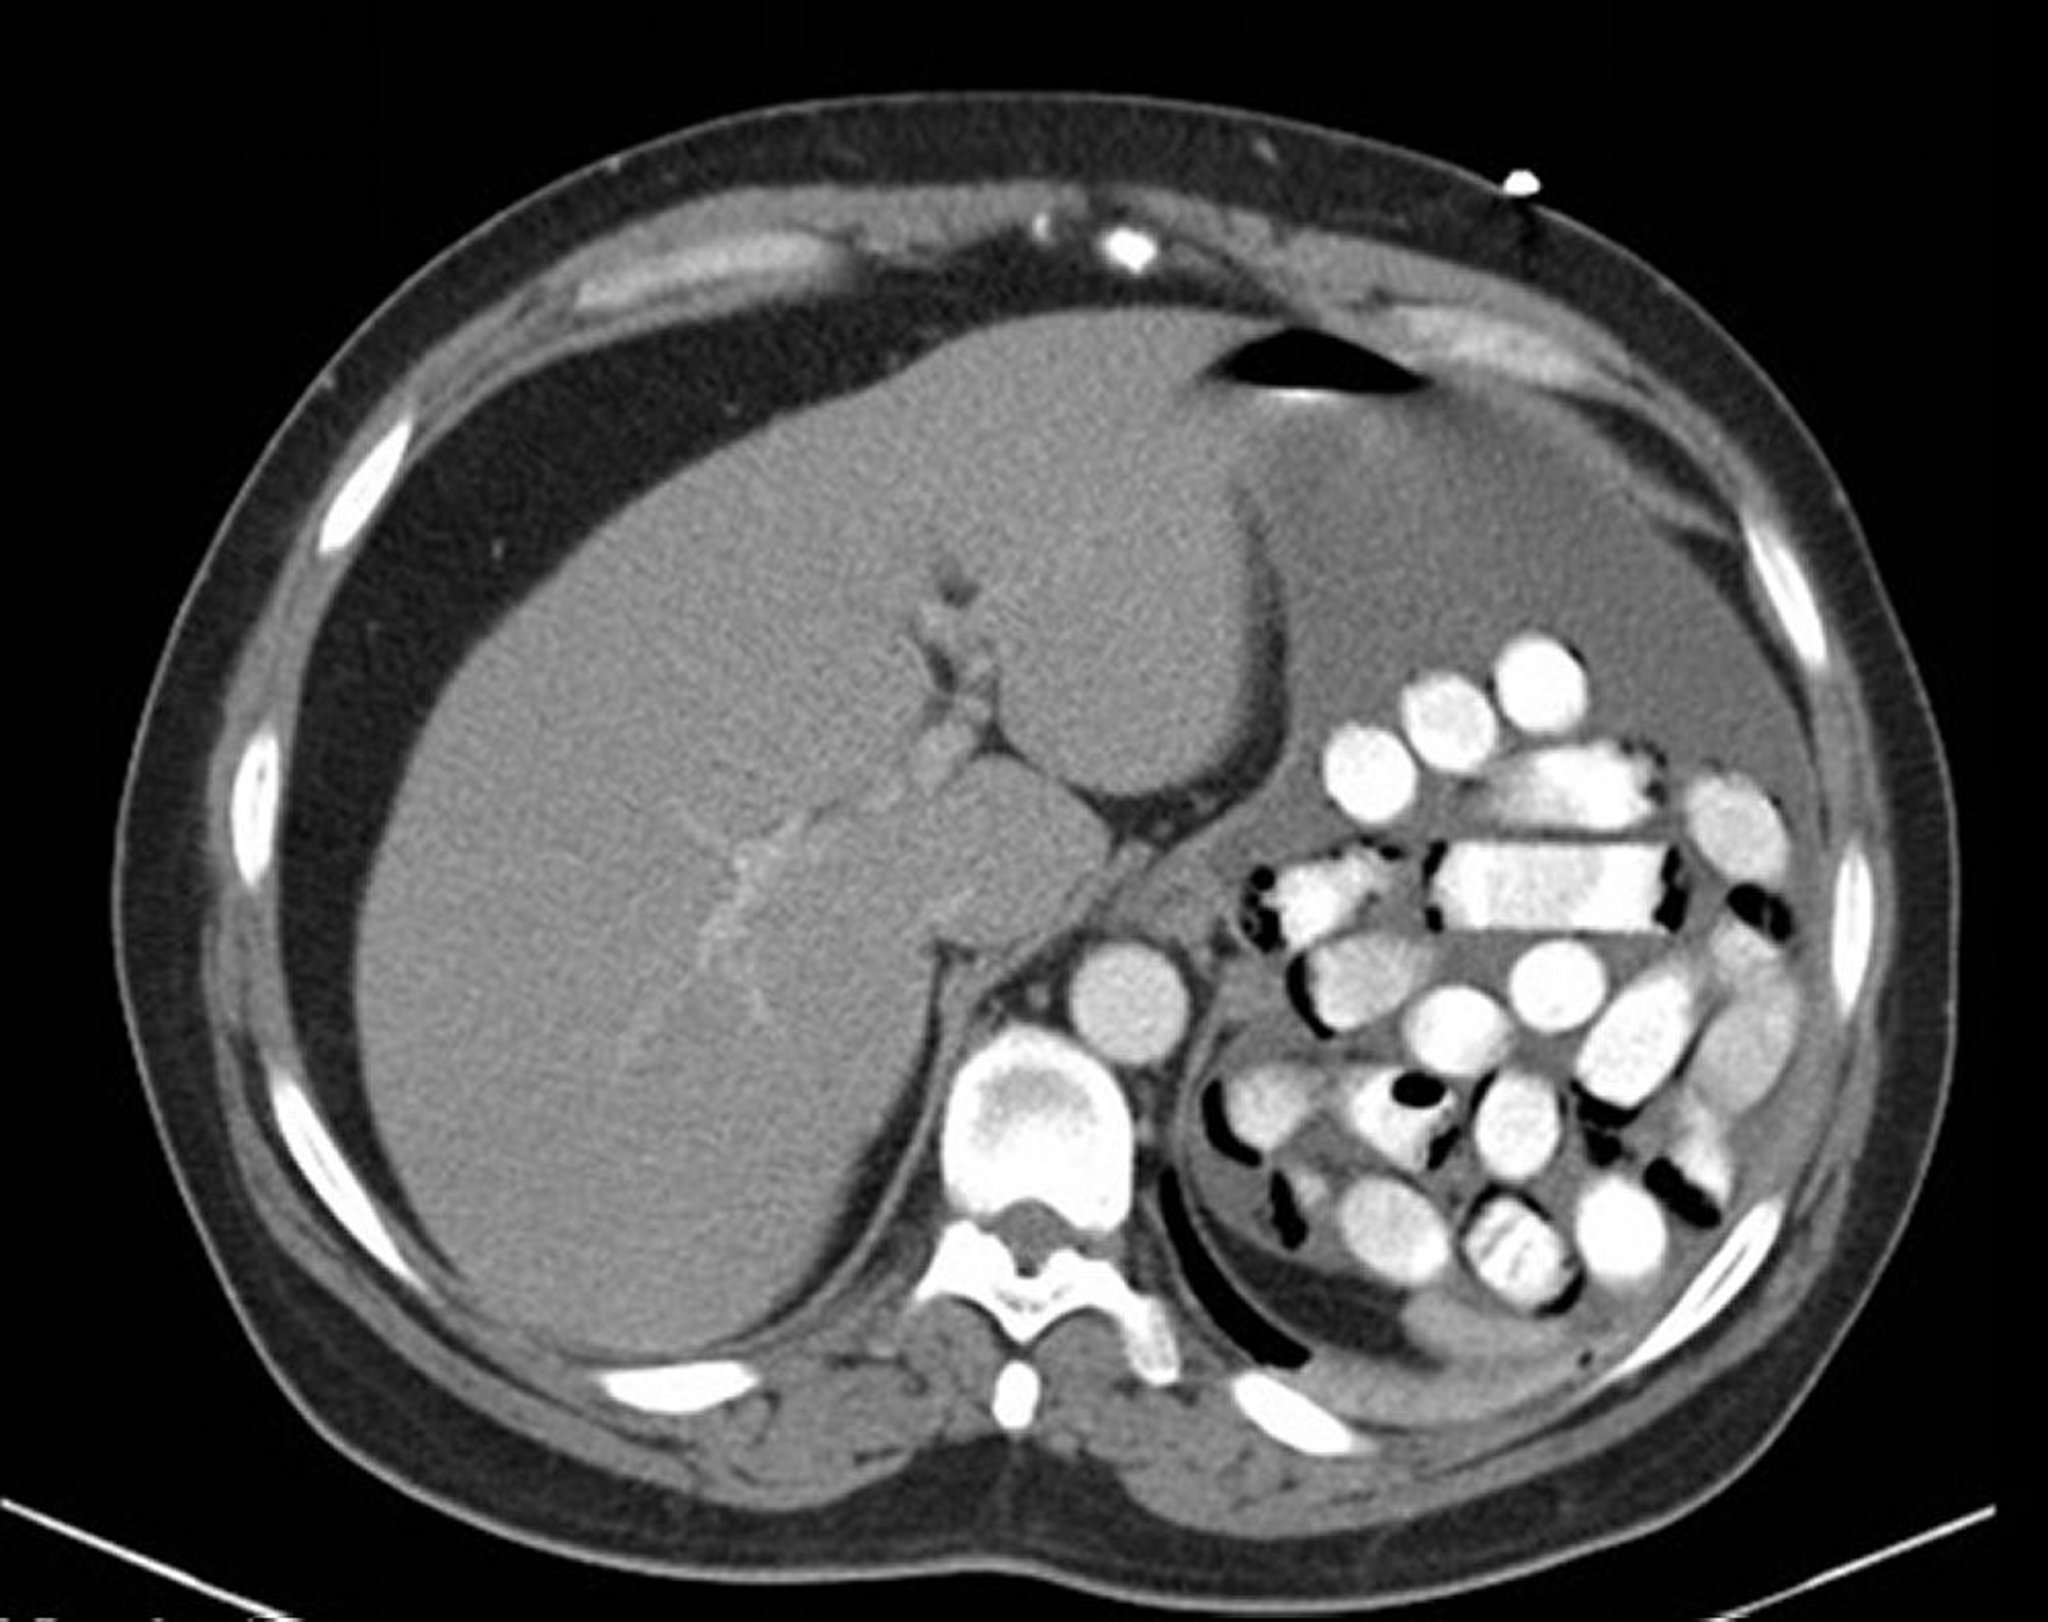

Fremdkörper im Magen (CT)

Dieses Bild zeigt Drogenpäckchen im Magen.

Abbildung zur Verfügung gestellt von Alan Gingold, DO.